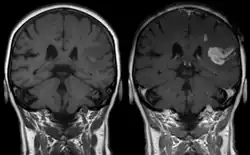

Magnetic resonance imaging

Gadolinium-based pharmaceuticals alter the relaxation time, and hence spectral line shape, of those protons that are in water molecules that are transiently attached to the paramagnetic atoms, resulting contrast enhancement of the MRI image.[12] This allows better visualisation of some brain tumours.[12]